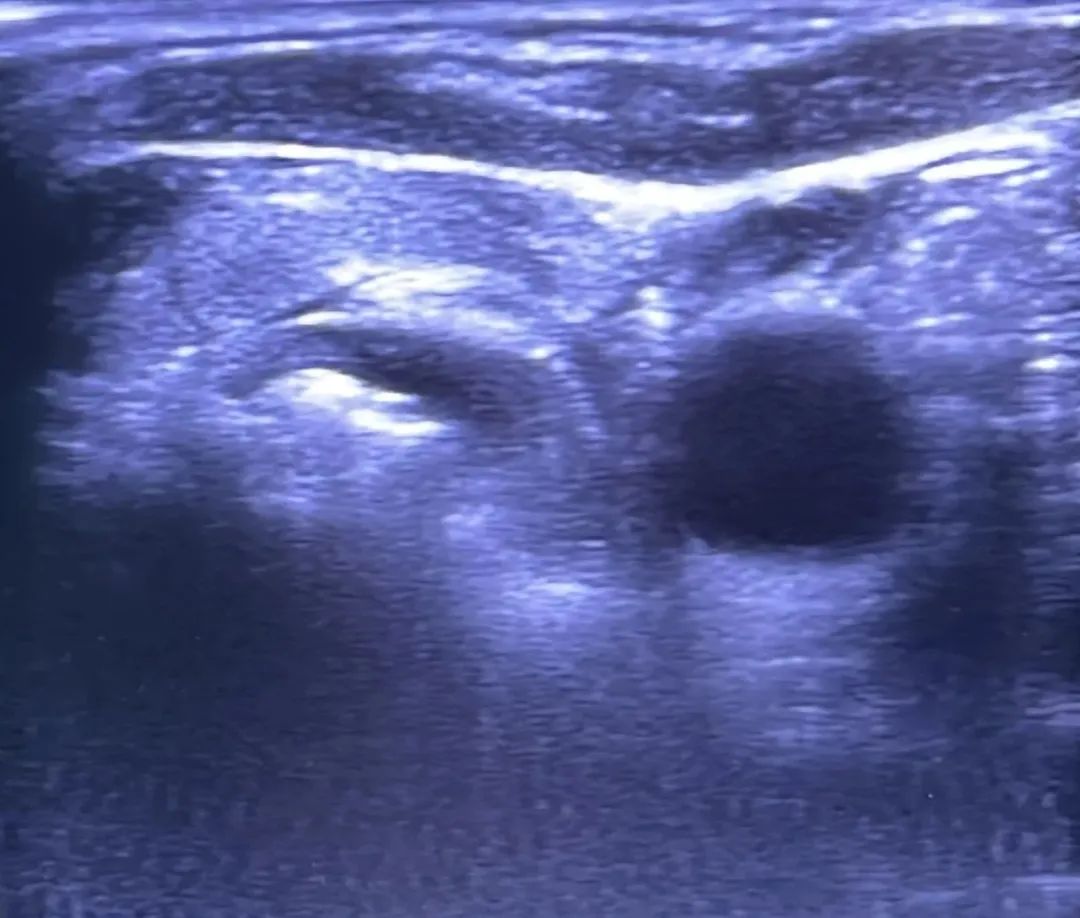

河南省人民医院常志扬教授(介入超声科副主任医师):擅长甲状腺结节微创消融术。

河南省人民医院常志扬教授为患者行甲状腺射频消融术

术前

术后